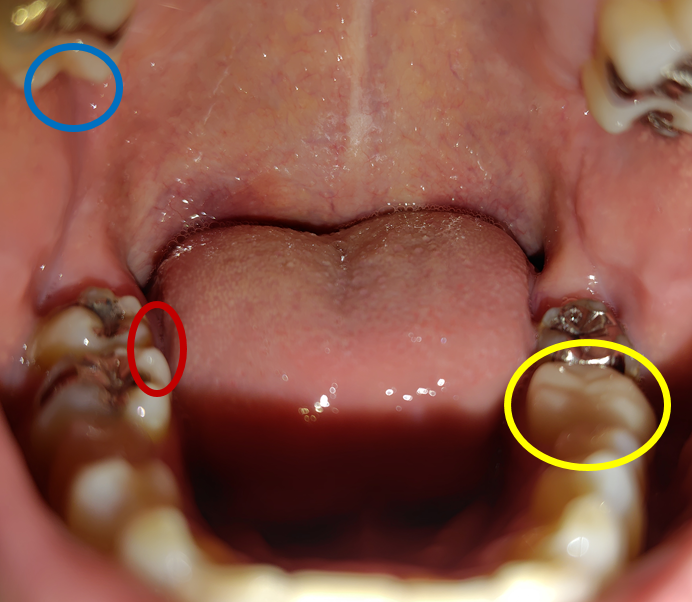

腱鞘炎による右腕の痛みに加え、人差し指も動かせなくなり、約2か月後には人差し指にうっ血が見られるようになりました。

うっ血がひどくなり、症状の悪化が続いてしまったため、6か月後にはある医師からは、「これ以上悪化したら、責任を持って切除しましょう」と親切心からおっしゃいました。